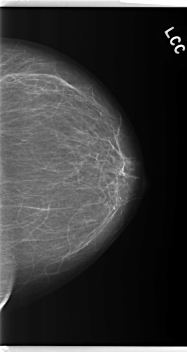

C_0276_1.LEFT_CC

LEFT_CC LINES 5968 PIXELS_PER_LINE 3168 BITS_PER_PIXEL 12 RESOLUTION 50 NON_OVERLAY